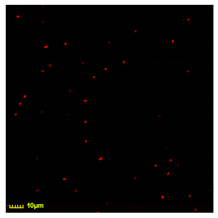

The macrophages exhibit varying degrees of phagocytic activity towards different strains of E. coli cells, as depicted in Figure 7, which presents CLSM images of CD206+ macrophages from BALF after a 4 h co-incubation with diverse E. coli strains. The degree of phagocytosis is significantly influenced by the morphological features of the bacterial surface. Relative indexes of the phagocytosis degree to the diverse standard bacterial strains (E. coli) can be considered as a parameter for the fingerprint analysis for the evaluation of the Mph subpopulation profile in BALF. Specifically, the highest value of the number of phagocytized bacteria is achieved for the strain JM109, characterized by the pronounced presence of protein fimbriae and pili that actively adhere to the macrophage surface before being engulfed. The phagocytic activity of macrophages against the MH-1 strain is less pronounced. Other strains display a lower phagocytic efficiency. Across all strains, the average number of phagocytized bacteria per macrophage ranges between five and six.

Figure 7.

Confocal laser scanning microscopy images of CD206+ macrophages derived from BALF after 4 h of incubation with different E. coli cells. Macrophages were stained with FITC anti-CD206 ligand (HPCD-PEI1.8-triMan-FITC)—green channel (λex,max = 488 nm; λemi = 505–555 nm). E. coli cells were stained RFP—red channel (λex,max = 559 nm; λemi = 575–625 nm).